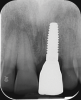

Fig 13. Radiograph after loading, showing solid bone remodeling within the machined implant neck area.

Figure 13